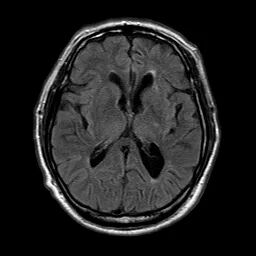

术前影像

颅脑CT:颅内多发腔隙性梗塞灶。

颅脑磁共振+头颈MRA:未见新发梗死;右侧颈内动脉C1段重度狭窄。